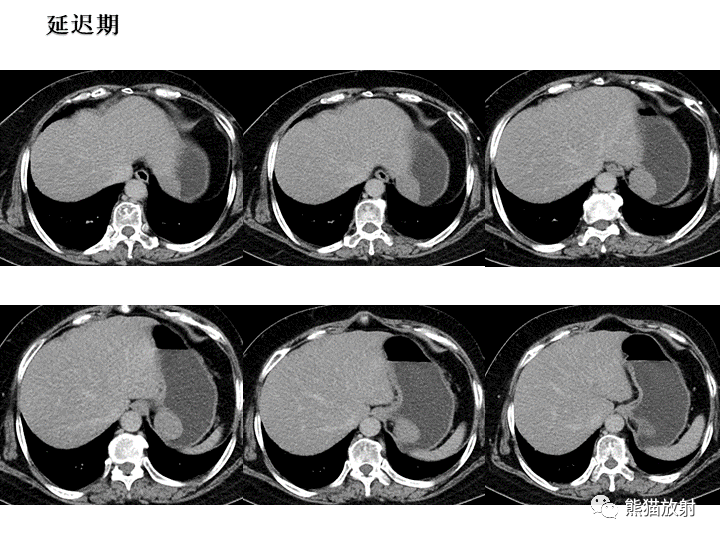

【病例】胃间质瘤VS神经鞘瘤-4